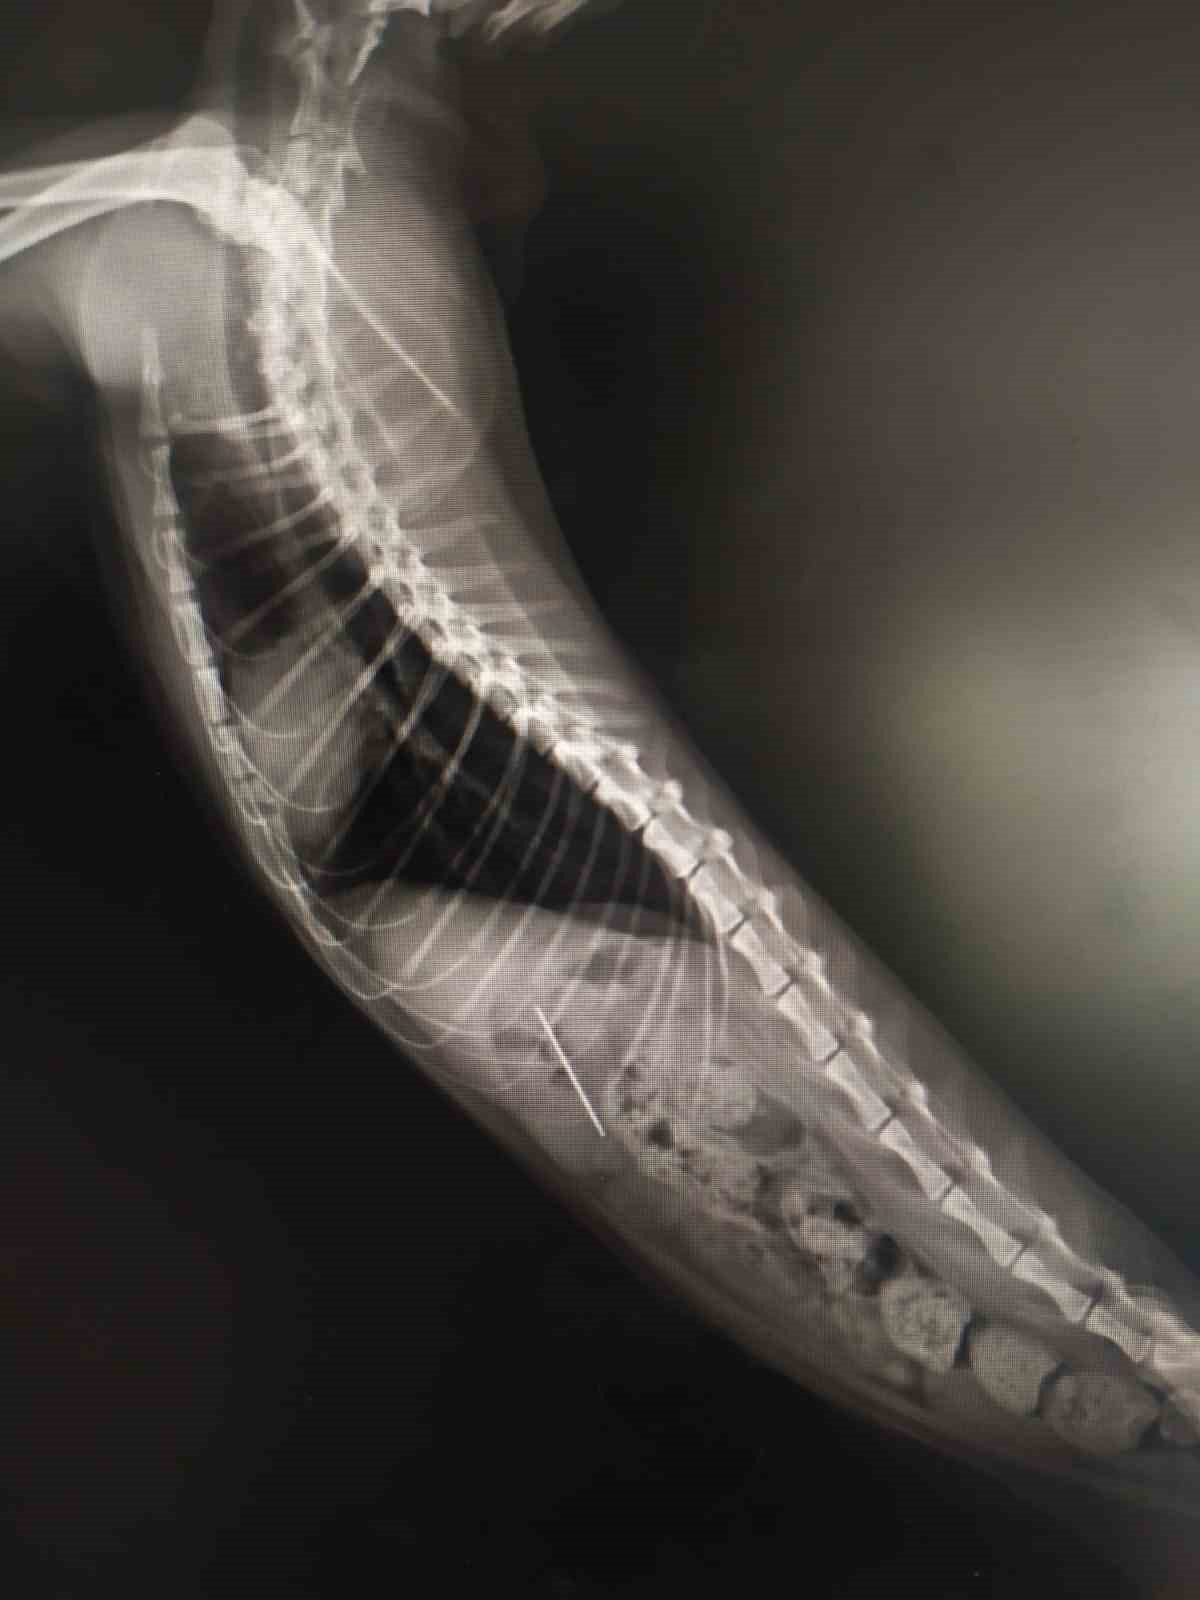

ÇEKİLEN RÖNTGENDE DİKİŞ İĞNESİ YUTTUĞU GÖRÜLDÜ

Bolu'da kedisinin rahatsızlandığını fark eden bir kişi veteriner hekime başvurdu. Edinilen bilgiye göre, özel bir veteriner kliniğinde muayene edilen kedinin röntgeni çekildi. Kedinin midesinde dikiş iğnesi olduğu görüldü. Endoskopiyle dikiş iğnesi kedinin midesinden çıkartıldı. Bir süre veteriner kliniğinde müşahede altında tutulan kedi taburcu edildi.